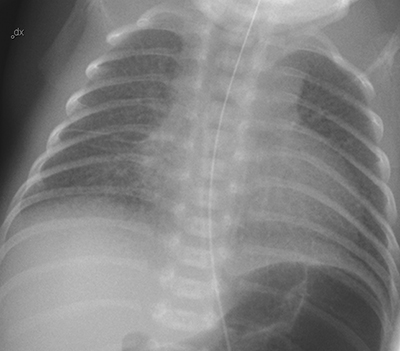

Röntgen differentierar mellan PAS och RDS även om blandbilder förekommer, särskilt i gestationsveckorna 30-33. Det är också viktigt att röntga för att identifiera infiltrat som vid pneumoni, täta atelektaser eller luftläckage/pneumothorax.

RDS – Karaktäristisk röntgenbild med nedsatt lufthalt, fingranulär teckning och luftbronkogram. Man ser även ofta att esofagus står öppen som tecken till att lungan är stel.

PAS – karaktäriseras av hyperinflation, ofta med nedpressad, platt diafragma. Stråkiga infiltrat sekundärt till kvarvarande lungvätska vätska i interlobärfåror och pleurasinus kan ses.